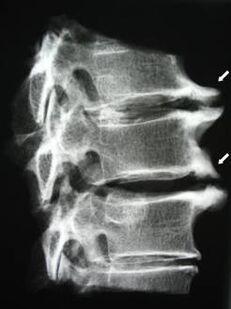

In the initial stages, MRI is used to detect osteochondrosis.Radiography can then be used to diagnose the pathology.On X-rays of the cervical spine, the distance between vertebrae decreases, pathological changes in the facet joints, and osteophyte hyperplasia become apparent.

| cervical osteochondrosis | Pathological changes occur in one or more spinal motion segments.Impaired spinal mobility, myofascial pain syndrome, and spinal cord root compression | Neck pain, paresthesias, and movement disorders, spreading to the back of the head and upper limbs.Detection of characteristic changes in the spine (osteophytes, shortening of the distance between vertebrae, signs of damage to the intervertebral joints) by MRI and X-rays |